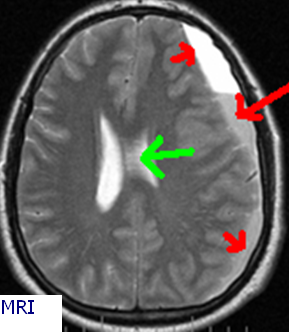

Bộ Não được bao quanh bởi ba lớp lót bảo vệ, lớp ngoài cùng là màng cứng. Chấn thương đầu có thể gây chảy máu ở vị trí giữa các màng cứng và bộ não. Chảy máu thường xảy ra từ vị trí tĩnh mạch bị thương trong màng cứng, gây áp lực lên não dẫn đến tổn thương não. Chảy máu có thể được nhận ra ngay lập tức nếu có tụ máu cấp tính dưới màng cứng, hoặc nhiều tuần sau Chấn thương ban đầu với tụ máu mạn tính dưới màng cứng. Các triệu chứng có thể khác nhau, như tê liệt hoàn toàn, hôn mê hoặc thay đổi nhẹ trong hành vi. Bệnh thường xảy ra ở độ tuổi 50-70 và bất kỳ rối loạn nào ngăn chặn sự đông máu bình thường đều làm tăng nguy cơ mắc bệnh này.

Chụp cắt lớp vi tính (CT Scan) đầu là xét nghiệm hình ảnh phổ biến nhất.

Xét nghiệm công thức máu toàn bộ (CBC), bảng chuyển hóa toàn diện (CMP), chụp cộng hưởng từ (MRI).